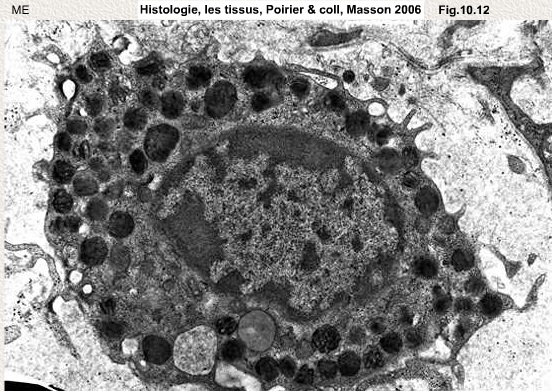

mastocyteME.jpg